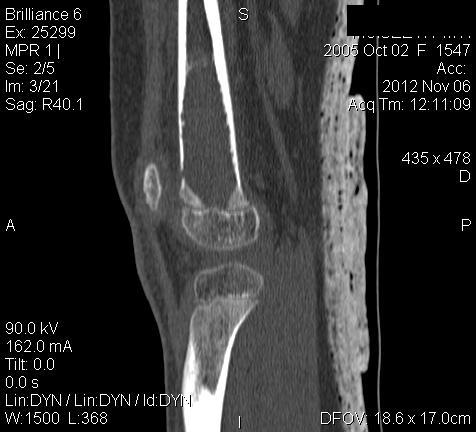

Уважаемые коллеги,

3 месяца назад в отделении была прооперирована девочка 7 лет с

клинико- рентгенологической картиной аневризмальной кисты (открытая

биопсия). Гистологическое заключение местных гистологов и ФНКЦ им. Д.

Рогачева -аневризмальная киста. 2 недели назад девочка взята на костную

пластику - на операции полный лизис костной ткани циркулярно на

протяжении 10 см от эпифиза на 10 проксимальней и массивное

артериовенозное крововтечение из оставшейся надкостницы .

неоднозначна. ФНКЦ им. Д. Рогачева дает прежний результат , ФГБУ РОНЦ НН

Блохина -телеангиэктатическая остеосаркома, онкологи из института

Герцена - киста .Как быть дальше. Кому верить и что делать? Заранее